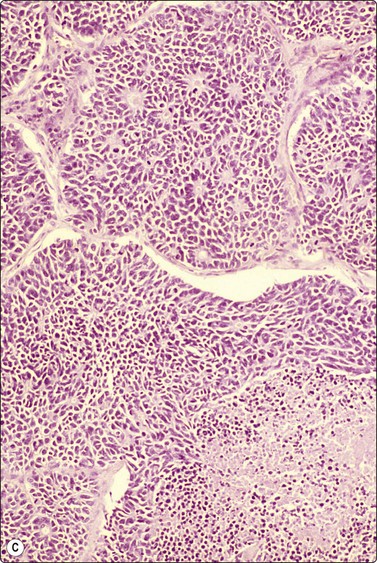

image image image

Fig. 8.28 High-grade neuroendocrine carcinoma; small cell carcinoma

(A, B) Smears showing ‘intermediate’ morphology. Loose aggregates of fragile cells with traumatization artifact and nuclear molding but some background cytoplasm (A, Pap, MP; B, H&E, HP). (C) Tissue section of resected peripheral stage 1 small cell carcinoma (H&E, HP).

image image image image image

Fig. 8.29 High-grade neuroendocrine carcinoma

Variable morphology including small cell and large cell patterns. (A) Low-power smear appearances of small cell carcinoma; (B) Higher-power examination shows some large cells with prominent nucleoli (A, H&E, LP; B, H&E, MP). (C,D) Tissue sections of resected peripheral stage 1 tumor showing areas of geographic necrosis and a predominance of large cells with prominent nucleoli (C, tissue section, H&E, LP, Inset, HP; D, tissue section, H&E, HP). (E) Positive immunostaining for chromogranin in resected specimen (E, tissue section, IPOX, HP).

This group of lung carcinomas is the most aggressive of the common types, having a mean survival of less than 6 months without treatment. Small cell carcinoma is virtually unheard of in non-smokers, while for carcinoid and atypical carcinoid the smoking association is much weaker. It is important to categorize this neoplasm accurately because, in general, chemotherapy rather than surgery will be used in management. In addition, chemotherapy regimens are different from those used for inoperable non-small cell carcinomas. This group is fairly homogeneous in terms of its biology but is more heterogeneous morphologically. Attempts at morphological subclassification have been made; however, the larger ‘intermediate’ and smaller ‘oat cell’ subtypes are not reliably separable by expert pathologists and do not have significantly different behavior or response to therapy. The latest WHO classification therefore does not subcategorize small cell carcinoma although it does recognize mixtures with other types of carcinoma.217

Cell pleomorphism is so distinctive that a diagnosis of malignancy is seldom in doubt (Figs 8.25-8.27). The most immediate impression is the absence or sparseness of cytoplasm rather than the small size of the neoplastic cell (Figs. 8.26 and 8.27). In fact, the cell nuclei may appear larger than similar cells in sputum and this may mislead one into making a diagnosis of non-small cell carcinoma. This difference in size between sputum and aspirated material is due to degenerative changes and shrinkage in sputum. It is sparseness of cytoplasm rather than size which is the most helpful initial clue in differentiating the lesion from other pulmonary carcinomas.

The combination of dispersal with clustering is also important, especially when other small cell neoplasms enter the differential diagnosis (Fig. 8.25). Lymphomas generally do not display such cell cohesion, although large fragments may be dislodged, and in some cases lymphoid cells may form clusters or packets.

Fragility of nuclei is emphasized by tear-drop cells or streaks of smeared nuclear material,226 and the close nuclear apposition and molding so commonly seen in sputum are also evident (Figs 8.26 and 8.27). Uniform coarsely granular ‘salt and pepper’ nuclear chromatin is also a well-recognized feature of this cancer in other sites, but one point of difference from sputum is the frequency of small nucleoli in aspirated material; they are less commonly seen in sputum. This may also be related to the better preservation of cells removed directly from tumor; small nucleoli are also often seen in bronchial brush material. Mitotic figures are usually easily found.

Although ‘intermediate’ small cell carcinoma is no longer recognized as a separate category in international classifications, we find it a useful concept to highlight the occasional difficulty in distinguishing between small cell and poorly differentiated non-small cell carcinomas (Figs 8.28 and 8.29). There is overlap in nuclear size between small and large cell carcinomas and a tendency for inexperienced cytologists to include small cell carcinomas with larger than expected nuclei in the non-small cell category. In general, if the nuclear features of a problematical tumor are those of small cell carcinoma – that is, granular chromatin without prominent nucleoli – the neoplasm will usually fall into the small cell carcinoma group histologically, whereas vesicular nuclei with prominent nucleoli would generally be evidence of non-small cell tumor. However, large cell neuroendocrine carcinoma does provide special problems. Our experience is limited but is similar to Yang et al. who described various morphologic patterns in this family of tumors, including small cell-like and mixed small cell/large cell-like FNAC patterns.37 Cell size is therefore an important criterion and one to be critically evaluated. Tumors with nuclei larger than 2–3 times the diameter of a lymphocyte may be classified as LCNEC histologically, even if nuclear chromatin pattern and other cytological features are similar to those of small cell carcinoma (Fig. 8.29). Our approach is therefore to first come to a diagnosis of ‘high-grade neuroendocrine carcinoma’ and then to critically examine cell size and morphology to determine the best category – ‘small’ or ‘large’. We do, however, agree with the idea propounded by Marchevsky et al.89 that the distinction between the two categories may be somewhat artificial in view of the overlap in cell size between the two groups. This is an area which requires close cooperation with oncologists and an acceptance of the limitations of cytological diagnosis. It may be necessary to base management on clinical and staging findings in conjunction with inconclusive cytological tumor typing in some cases.